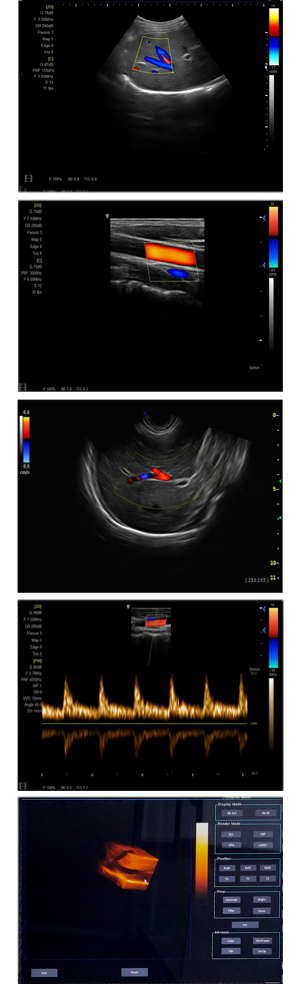

為高集成數(shù)字式彩色多普勒系列產(chǎn)品之一,廣泛實施于腹部,產(chǎn)科,婦科,血管,小器官,泌尿,新生兒和兒科等臨床,屬全身應(yīng)用型彩色多普勒儀器。

●全身應(yīng)用型包含2D/CFM/PDI/PW/ M等掃描模式;

●升級版可選配3D、反向諧波等高級功能。